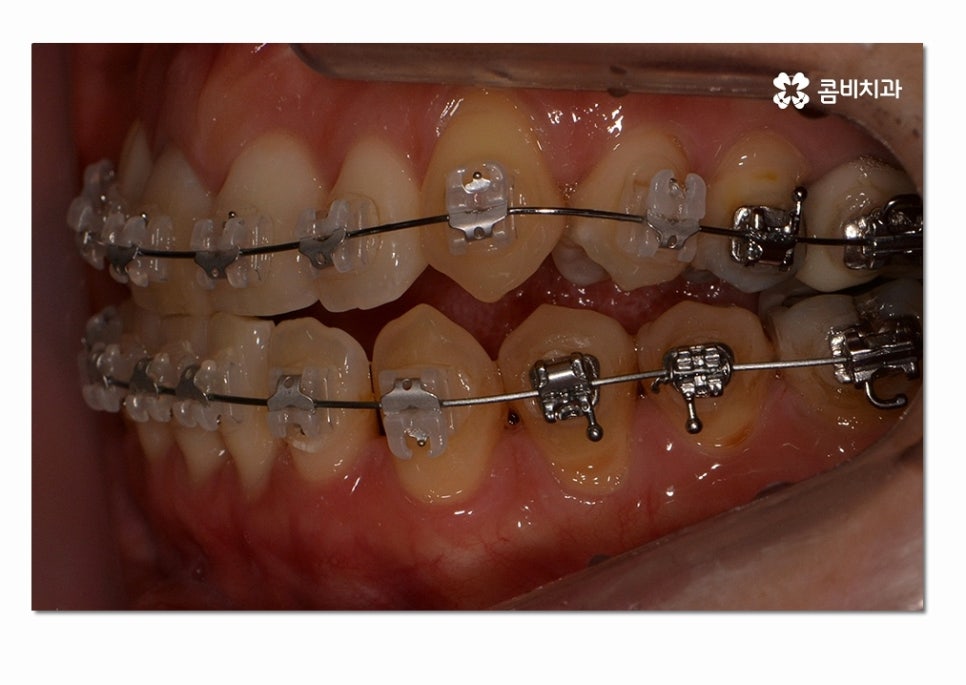

이렇게 옆면으로 보면 교합이 정상적으로 잘 맞물리지 않고

음식물을 골고루 씹어야 하는 어금니가 제대로

맞닿아 있지 않아서 불편함을 느끼게 될 수 있는데요.

이러한 3급 부정교합은 나이가 들수록 구강 내 충치 및 잇몸질환의

발생률을 높일 뿐 아니라 음식물을 제대로 씹지 않아서

만성적인 소화불량을 겪기 쉽고 발음상의 불리함이나

턱관절 장애로 이어지는 경우도 많기 때문에 성인 이후에도

교정을 통해서 심미성과 함께 교합, 건강에 대한 개선이 필요할 수 있어요.